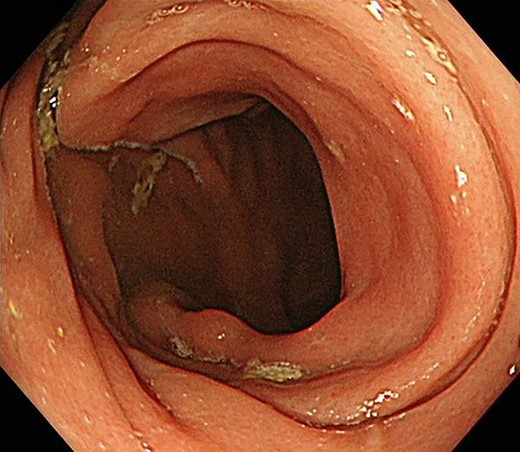

Contrast-enhanced computed tomography revealed a giant irregular mass (45 × 35 mm) in the abdominal wall (Fig. 2). No other intra-abdominal neoplasm were present; however, an irregular lung mass measuring 50 mm in size in the S10 region of the right lobe and a mass measuring 12 mm in size in the S1/2 region of the left lobe were found (Fig. 3). Total gastrointestinal endoscopy, including capsule endoscopy, revealed no neoplasm in the intestinal tract (Fig. 4a–c).